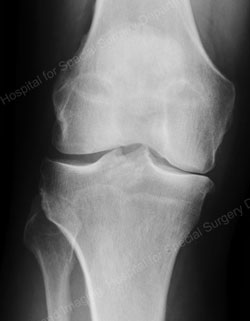

Figure: A valgus stress view shows an intact lateral compartment in a good candidate for a unicondylar knee replacement

The knee is made up of three compartments: the medial compartment (located on the inside of the knee), the lateral compartment (located on the outside of the knee), and the patellofemoral compartment (located in the front of the knee). In a particular group of osteoarthritis patients, however, the entire knee is not affected by the arthritis. In some patients, only the medial compartment (or, less commonly, only the lateral compartment) may be affected by the disease. For those patients, unicondylar (partial) knee replacement can be considered a treatment option. The term “unicondylar” refers to the replacement of only one section of the smooth bone ends (condyles) – the medial or lateral compartment – as compared to total knee replacement, which involves replacement of all three compartments.

In addition to these criteria, patients with a relatively good preoperative range of motion and a minimal amount of deformity were considered to be ideal candidates for a unicondylar knee replacement.